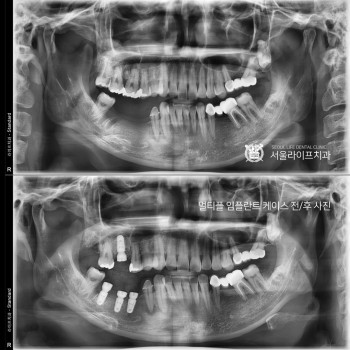

전체 임플란트 수술 케이스 전/후 사진

멀티플 임플란트 시술